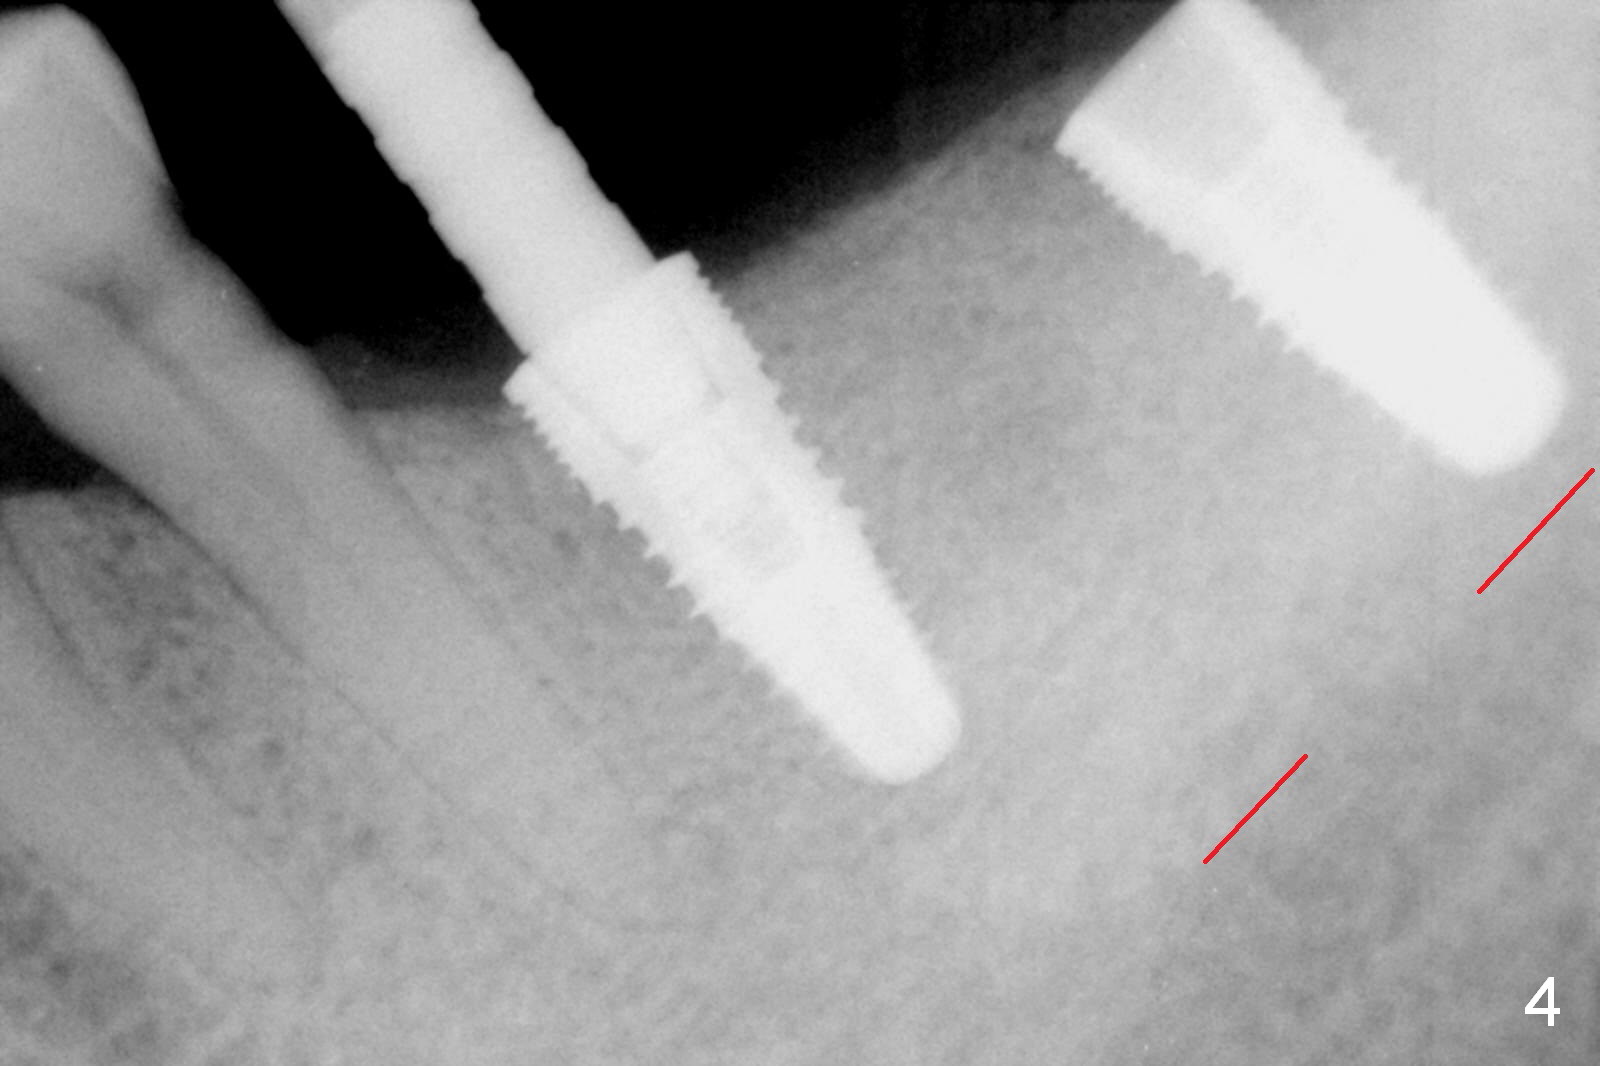

In fact, initial depth for #18 and 19 is 12 mm, quite close to the Inferior Alveolar Canal at #18 (Fig.3 (red dashed line: the superior border of the former). By mistake, the implant at #18 is placed a little deeper than necessary, since the buccal bone is inferior to the lingual one (Fig.4; 5.3x12 mm vs. 5.0x12 mm for #19). As planned, panoramic X-ray is taken immediately postop. Bone height at the 2nd molar decreases drastically as compared to that of the 1st molar, especially on the right side (Fig.5 (abutments: 6.8x5(2) mm for #19, 7.8x5(3) for #18, respectively)). For #30,31 implant placement, initial depth will be 10 and 8 mm, respectively. Follow it faithfully. The implant at #31 could be as large as 5.9 or 6.4 mm to compensate for the length.

One month later, the patient returns for #30 and 31 implant placement. As planned, the initial depth is 10 and 8 mm (Fig.6). What is unexpected is deficiency in ridge width. Narrower implants (as compared to those on the left) are placed (Fig.7: 4.5x12 and 4.5x10 mm). With shorter implants, the implants are later placed deeper (as shown by arrows in Fig.7) so that almost all of the microthreads are buried in the bone. It is expected that there is less chance of thread exposure postop. The later turns out to be true 3.5 months postop (Fig.8 with 6.8x5(3) mm abutments). It appears that the abutment margin is supragingival (white dashed line: gingival margin) and should be trimmed prior to impression. Or change the abutments to ones with shorter cuff. It may be so for those at #18 and 19 (Fig.9: 4 months postop). Custom full arch trays will be used for impression with bite registration. In fact the mesial margin of #19 abutment is ~ 2 mm subgingival. A longer-cuff abutment is used (6.8x5(3) mm) at #19 before impression.